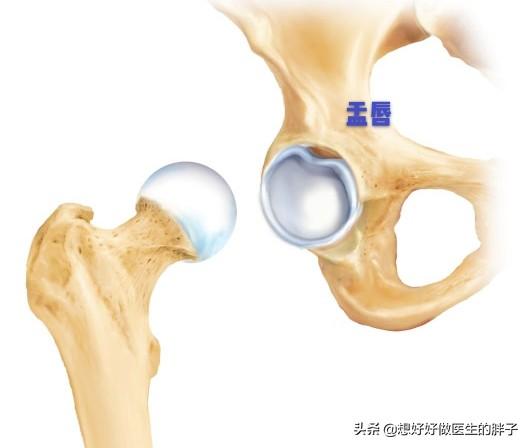

髋关节可以说是一个非常大的球窝关节,构成髋关节主要由髋关节的髋臼以及股骨的股骨头。大家可以把髋臼理解成一个碗,股骨头是一个光滑的球,股骨头在髋臼构成的这个小碗内做自由的活动。

但是如果这个小球活动的太自由,就会有可能导致髋关节的不稳定,所以我们的人体为了相对来讲更好的稳定髋关节,在髋臼的外缘形成了一层软骨结构,更好的帮助髋臼稳定关节,可以给股骨头在髋关节活动增加稳定性和保护,由于这个结构像嘴唇一样包绕着整个髋臼的周围,所以被命名为盂唇。